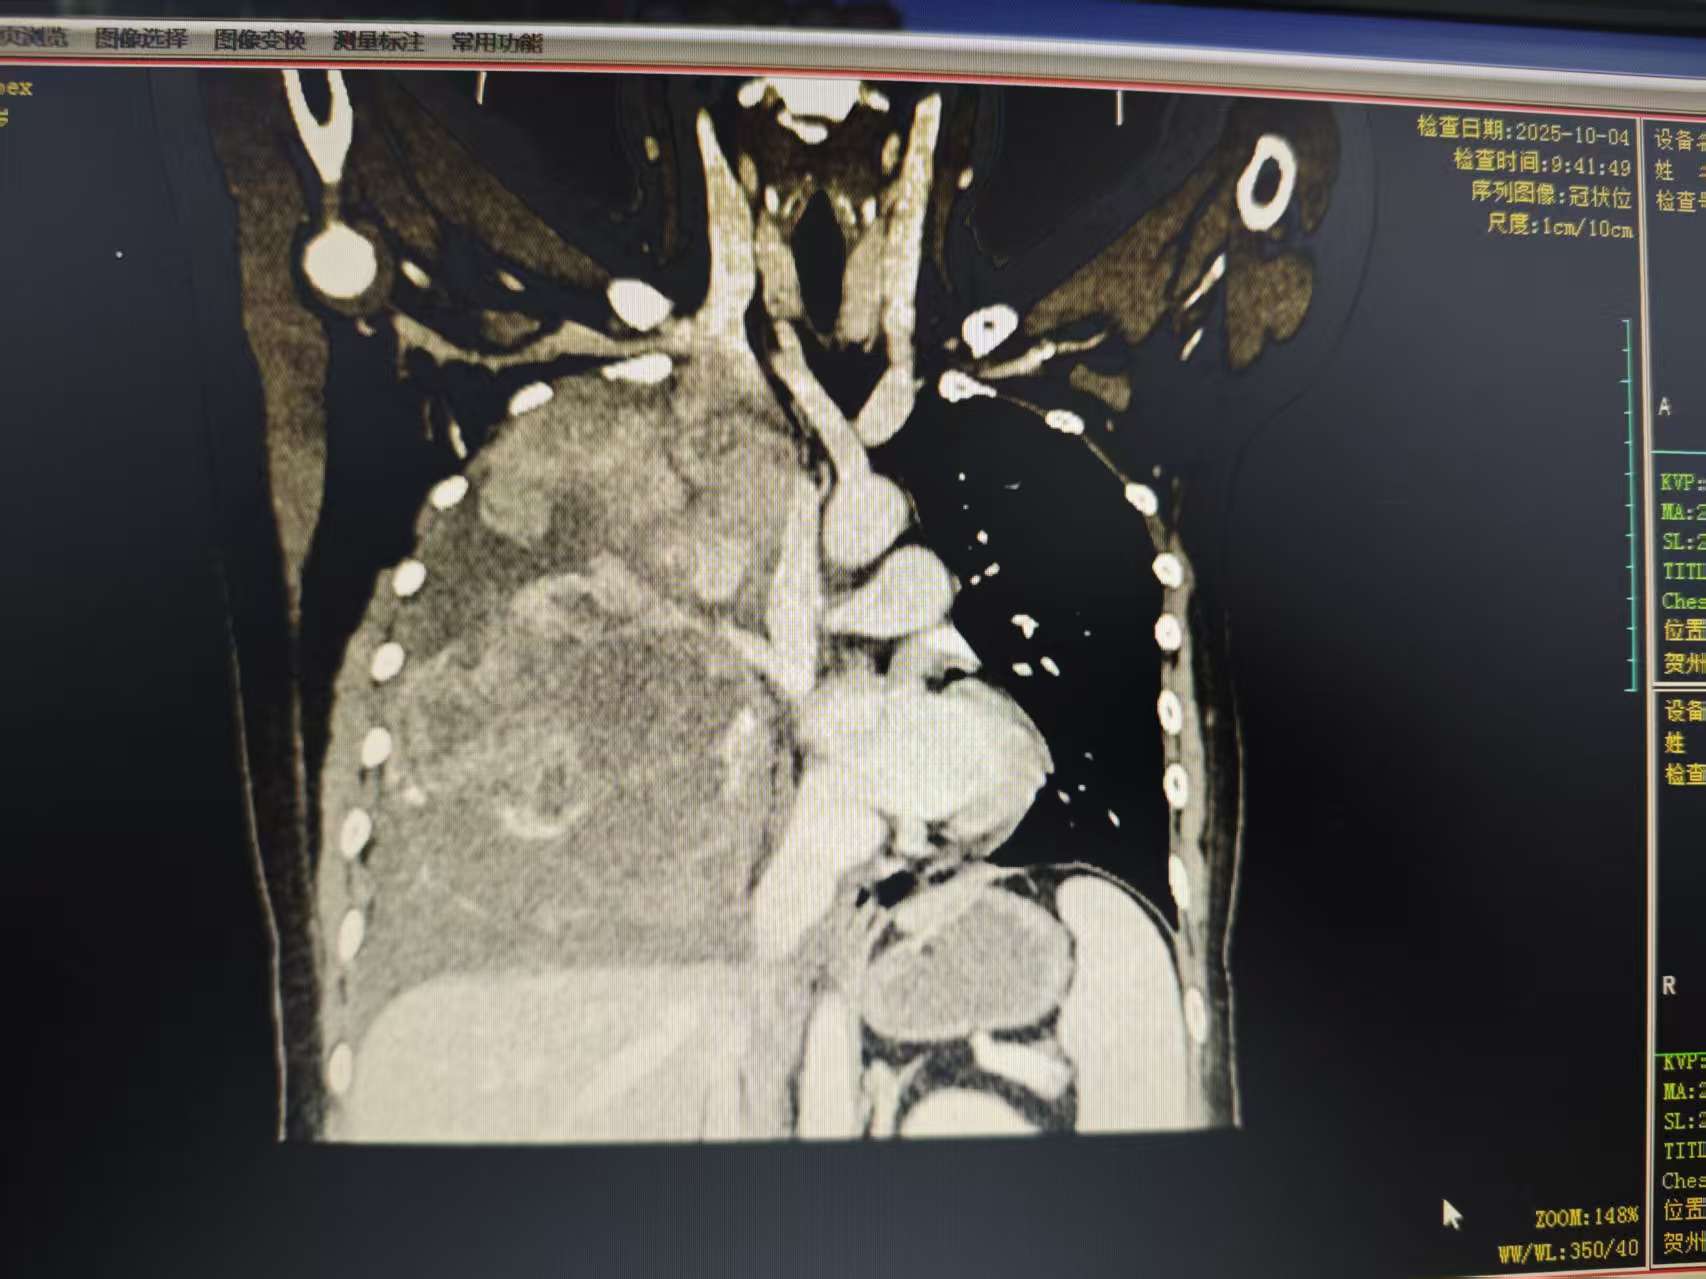

这位27岁的年轻女孩,最近几个月一直被反复的胸闷、咳嗽和气短所困扰。来到贺州市中医医院检查后,结果让人大吃一惊——她的右侧胸腔内,长了一个巨大的肿瘤。

这个“不速之客”体积惊人,长约30多厘米,几乎占据了整个右侧胸腔,将患侧的胸廓都撑大了,并导致右肺受压、体积缩小,还伴有胸腔积液。巨大的肿瘤压迫让她感觉 “连呼吸都成了负担”。